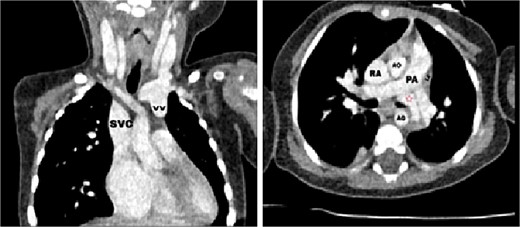

Transthoracic echocardiography (TTE) revealed an isolated supracardiac type of TAPVC, accompanied by a large ostium secundum atrial septal defect (ASD) measuring 9 mm, exhibiting a right-to-left shunt. Furthermore, there was evidence of dilatation in the right heart cavities and severe pulmonary hypertension (PHT = 65 mmHg). The common pulmonary confluence, measuring 12 mm in diameter, drained into the left innominate vein via a vertical vein. Confirmatory computed tomographic angiography (CTA) supported the diagnosis of supracardiac type TAPVC and identified stenosis along the venous pathway between the right and left pulmonary veins (Figs 1 and 2).

Axial (right) and coronal (left) postcontrast computed tomography sections: SVC: superior vena cava, VV: vertical vein, RA: right atrium, LA: left atrium, AO: aorta, PA: pulmonary artery, red star: The confluence of PVs.